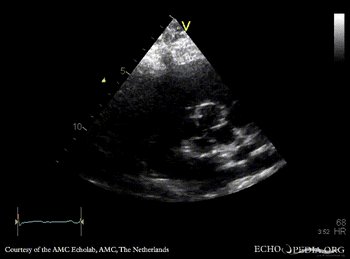

Quadricuspid aortic valve

Courtesy of: AMC Echolab, AMC, The Netherlands

PLAX: dilated left ventricle and aortic root in patient with quadricuspid aortic valve PSAX: quadricuspid aortic valve